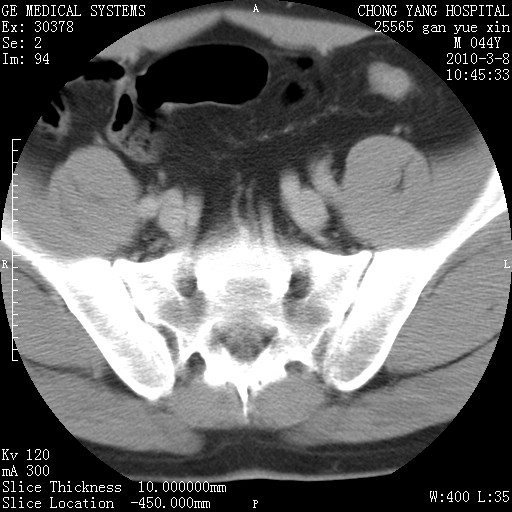

标题: CT24940:主动脉增强,典型病例。 [打印本页]

标题: CT24940:主动脉增强,典型病例。

夹层动脉瘤。

动脉夹层

夹层动脉瘤,典型

主动脉夹层。

动脉夹层的分型:

⒈debakey分型:根据主动脉夹层累及部位,分为三型:ⅰ型:原发破口位于升主动脉或主动脉弓部,夹层累及升主动脉、主动脉弓部、胸主动脉、腹主动脉大部或全部,少数可累及髂动脉。ⅱ型:原发破口位于升主动脉,夹层累及升主动脉,少数可累及部分主动脉弓。ⅲ型:原发破口位于左锁骨下动脉开口远端,根据夹层累及范围又分为ⅲa,ⅲb。ⅲa型:夹层累及胸主动脉。ⅲb型:夹层累及升主动脉、腹主动脉大部或全部。少数可累及髂动脉。

⒉stanford分型:a型:夹层累及升主动脉,无论远端范围如何。b型:夹层累及左锁骨下动脉开口以远的降主动脉。

夹层动脉瘤,少量胸水

夹层动脉瘤;左侧少量胸腔积液。

典型主动脉夹层。